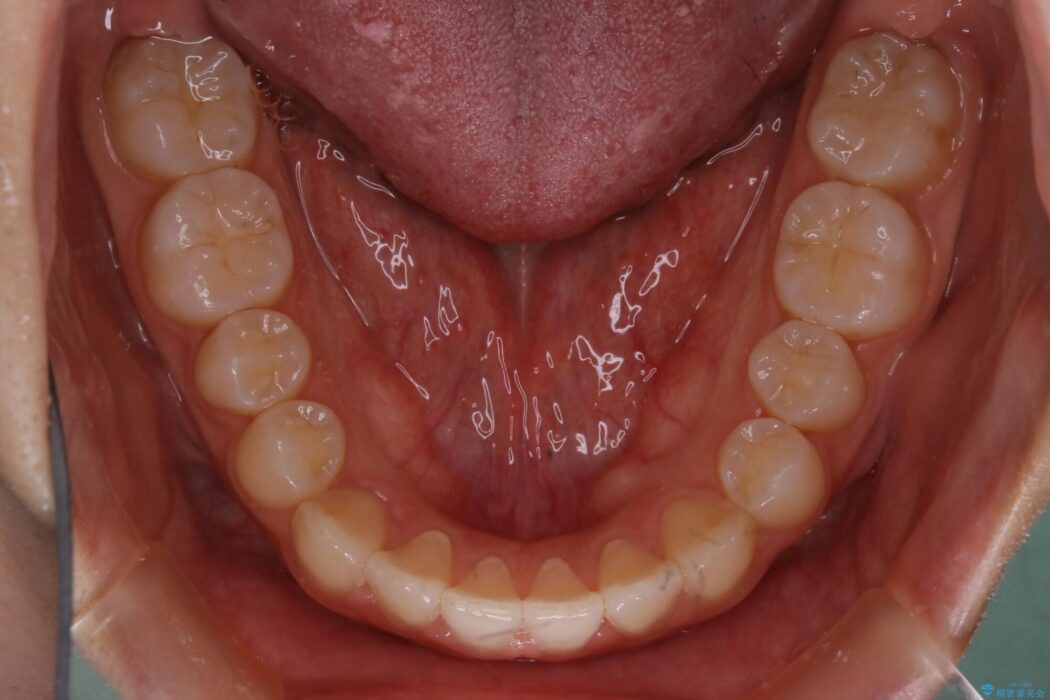

詳しく検査したところ、上顎の歯が舌側に倒れこんでしまっていることや歯列のガタガタなどにより口を閉じた時に上下の前歯の先端が接触してしまっていました。

よってまずは上顎の歯列を整えることから始め、前歯同士の衝突を改善してから、噛みこむ位置を本来あるべき後方へと調整することとしました。

今回のケースでは非抜歯での治療を行っています。